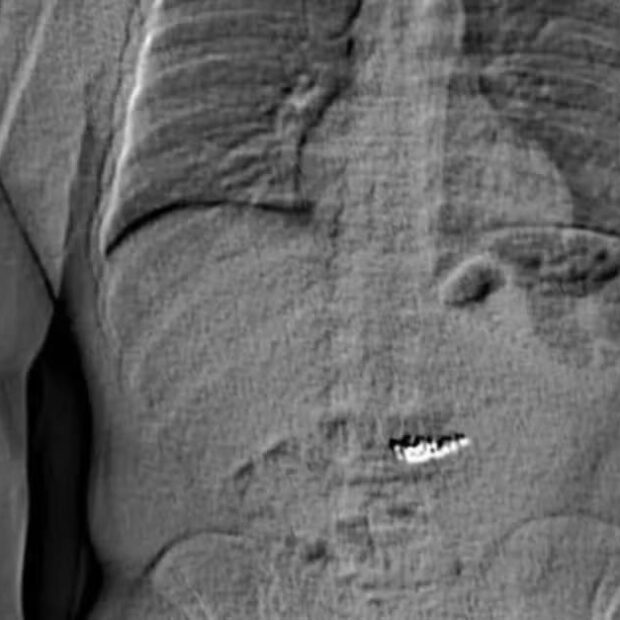

Um americano acusado de roubar US$ 769 mil em joias da Tiffany & Co na Flórida engoliu os itens antes de ser preso.

Jaythan Gilder, 32, fingiu representar um jogador da NBA para acessar peças valiosas e fugiu após lutar com funcionários. Rastreado pela polícia, foi interceptado e um raio-x revelou as joias em seu estômago.